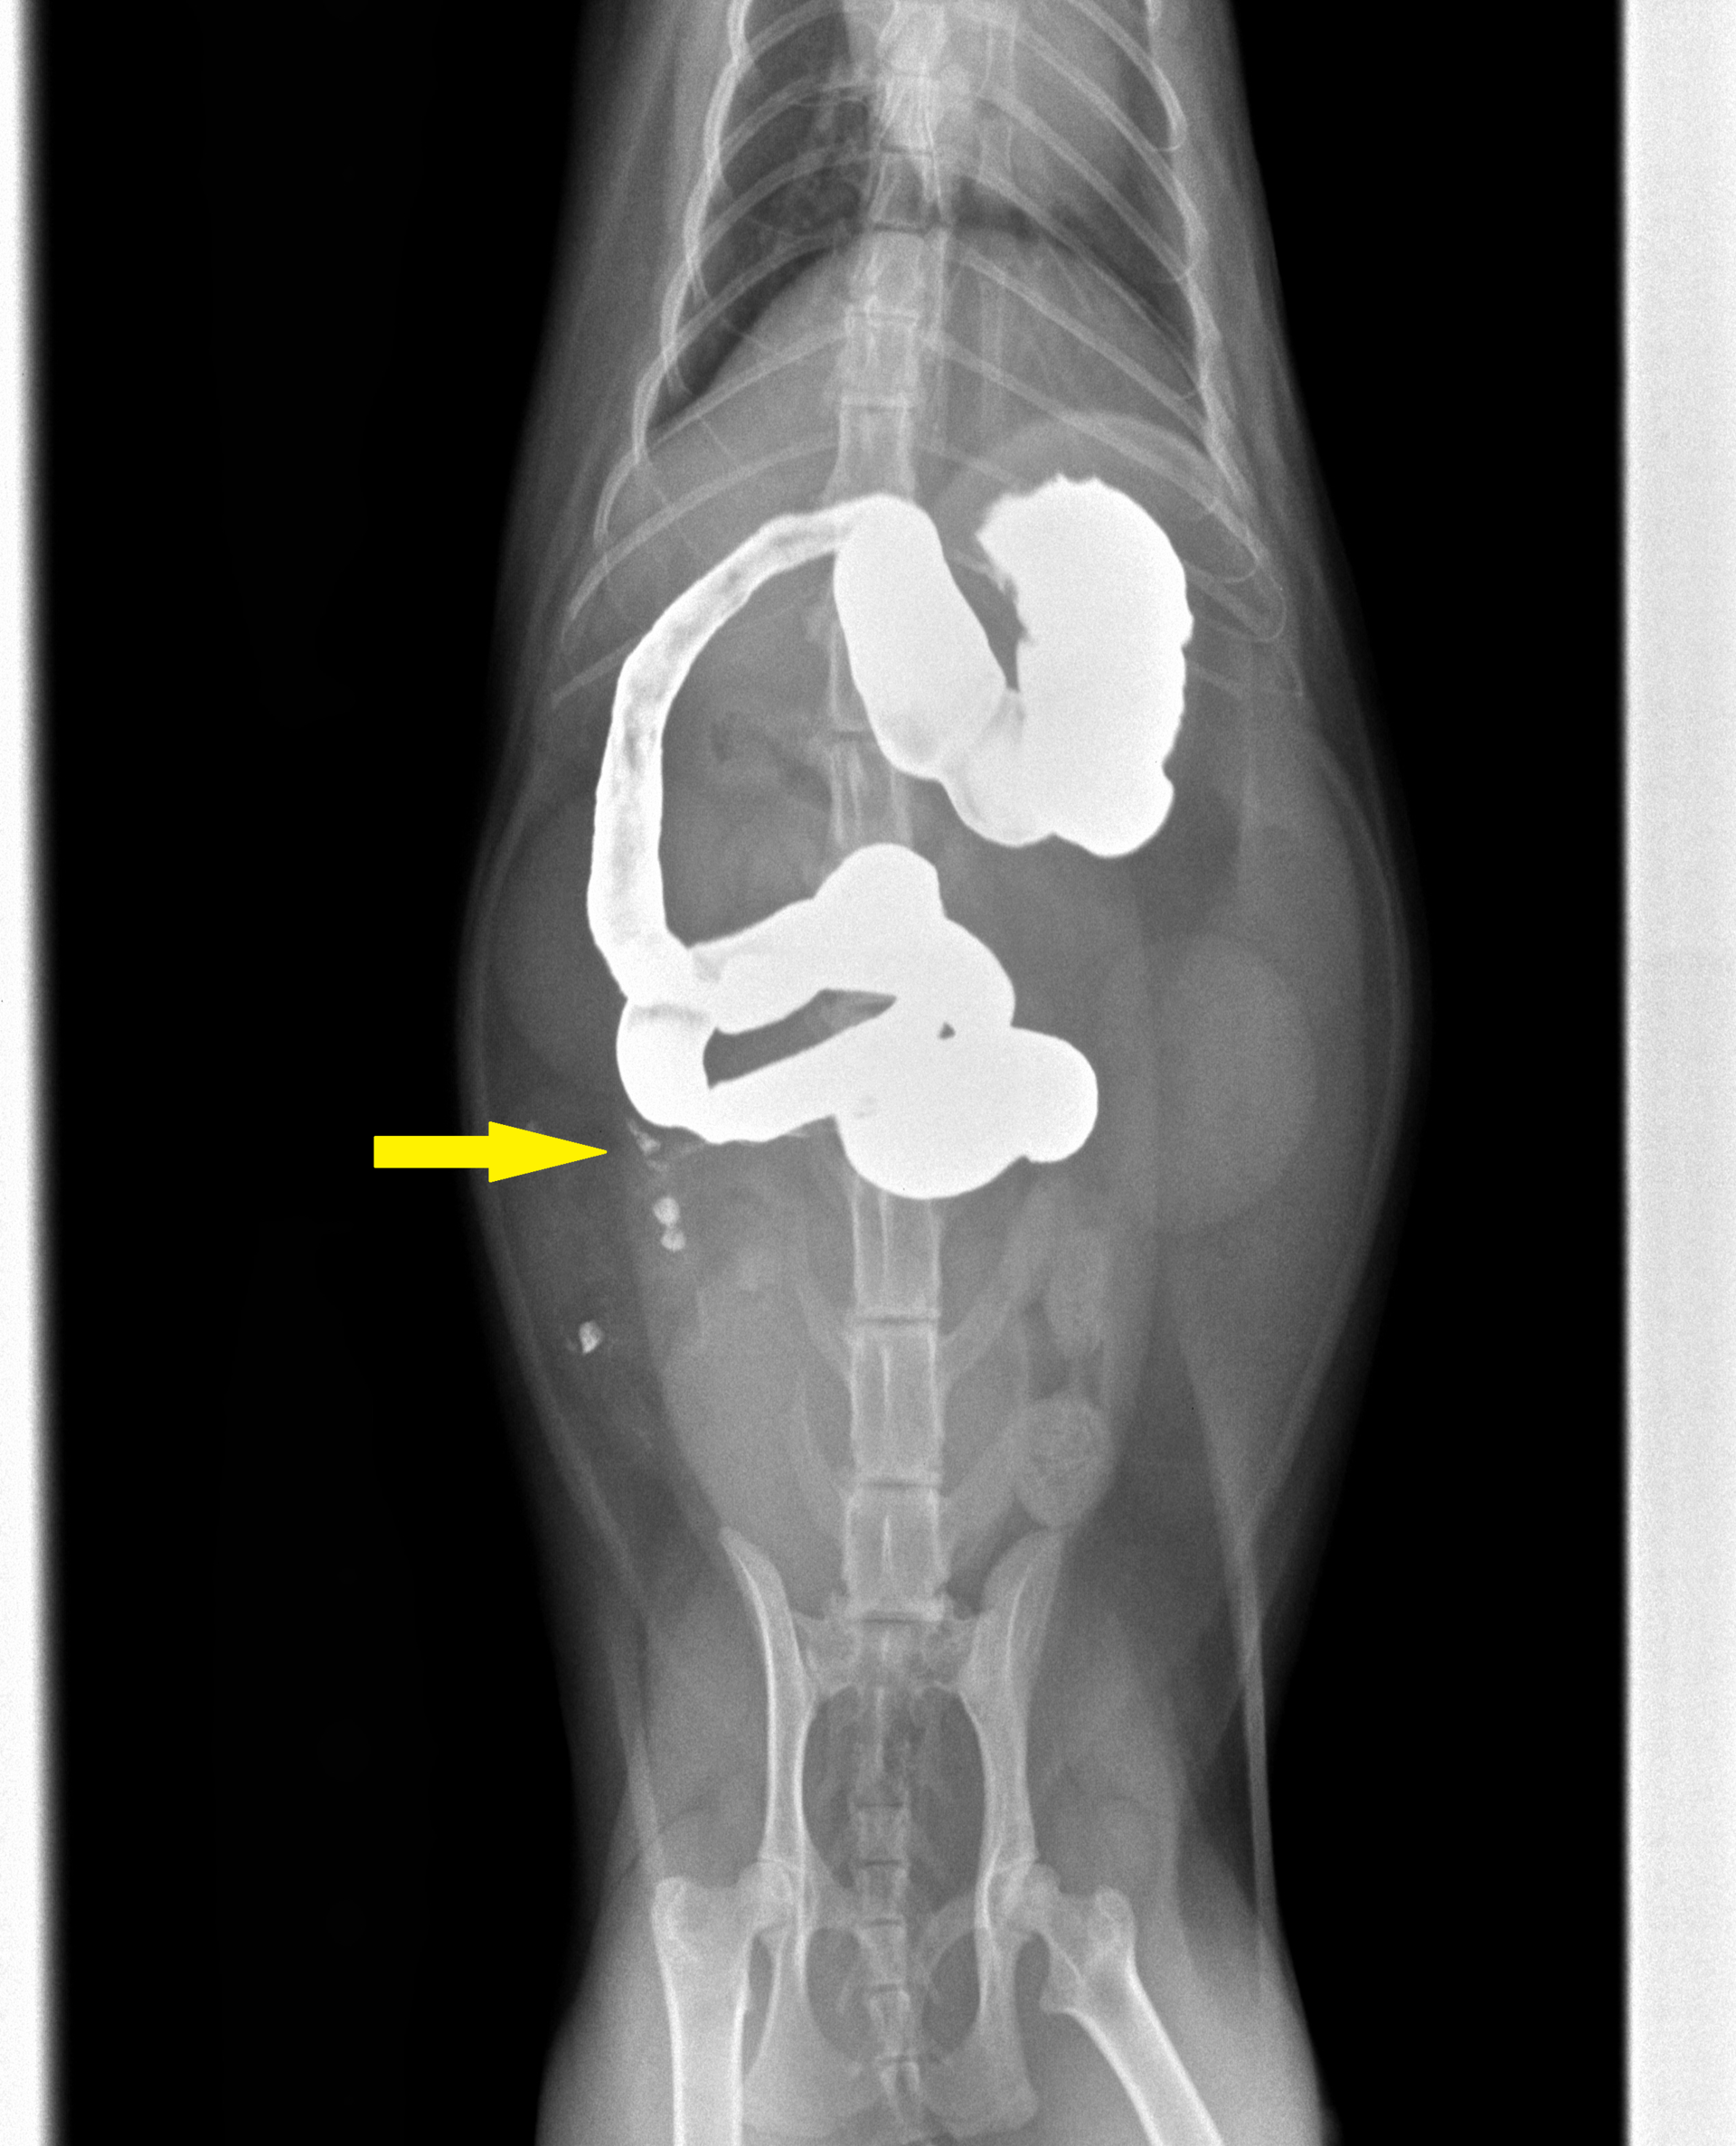

診察初日は点滴をし、その当日の絶食絶水を指示し、その日は自宅で様子を見ていただきました。しかしその次の日、嘔吐は治まらず吐き続けているということで来られました。そこで、異物がないかバリウム検査を行いました。その結果が下の写真です。

投与15分後

投与60分後

バリウムを投与後、15分も60分も同じところ(矢印)でストップして全く流れていないことがわかります。異物による通過障害が考えられたので、当日緊急手術となりました。その様子が下の写真です。